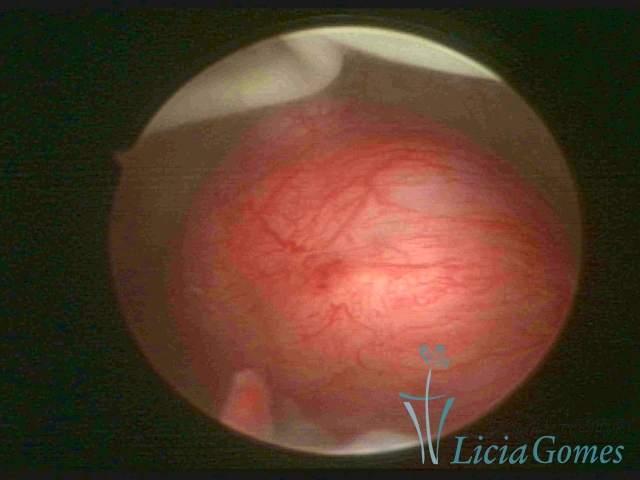

Cavidade uterina com DIU e muco claro acumulado